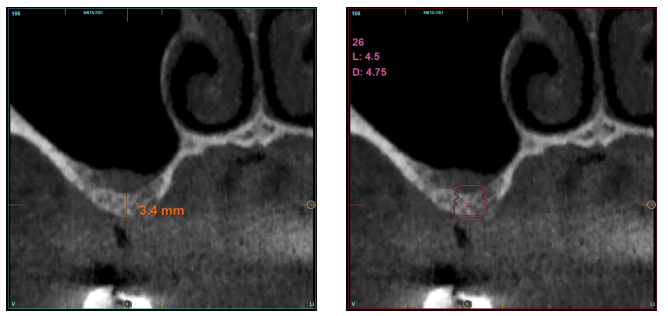

En todos los casos, se realizó un diagnóstico basado en modelos de estudio, exploración intraoral del paciente y realización de un Cone-beam analizado mediante el software específico BTI-Scan III (Biotechnology Institute, Vitoria, Alava, España).

La altura media del volumen óseo residual fue de 3,1 mm (+/- 0,3 mm con un rango de 3-4 mm). En todos los casos se realizó una elevación de seno transcrestal, con hueso autólogo particulado obtenido del fresado de la zona de generación del neoalveolo para la inserción del implante, siendo la media de esta elevación sobre el ápice del implante en milímetros de 2,8 mm (+/- 0,99 rango 1,9 -5 mm). En el TAC de control al año de carga de los implantes estudiados, se mantiene la ganancia ósea lograda, no observándose disminución del volumen ganado, únicamente tres casos mostraron una disminución de entre 0,4 y 0,5 mm del volumen inicial al final (Tabla).

En las Figuras 2- 19 se muestra uno de los casos incluidos en el estudio.

en altura de 3,4 mm, siendo más uniforme en esta ocasión en toda la zona de la cresta. Se planifica un implante de 4,5 mm de longitud y

4,75 mm de diámetro.